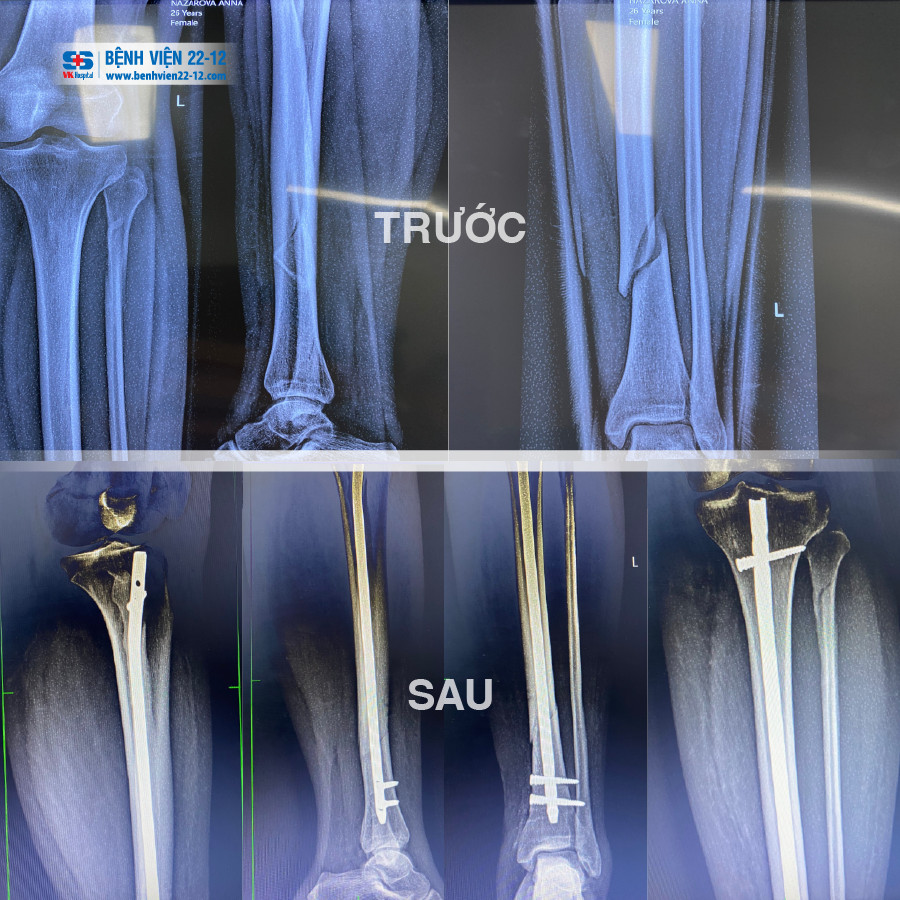

Sau khi được bác sĩ khám lâm sàng và cận lâm sàng, dựa trên kết quả chụp X-quang, bác sĩ chẩn đoán bệnh nhân bị gãy kín xương cẳng chân trái cụ thể gãy 1/3 giữa dưới xương chày và gãy 1/3 trên xương mác do tai nạn sinh hoạt. Các bác sĩ khoa Ngoại – Chấn thương chỉnh hình quyết định phẫu thuật kết hợp xương chày bằng đinh nội tủy (đinh SIGN), không mở ổ gãy dưới máy C-ARM cho bệnh nhân.

Các bác sĩ tiến hành rạch da dài 03cm kể từ cực dưới xương bánh chè, nắn chỉnh xương và đóng đinh nội tủy (đinh SIGN) dưới sự hỗ trợ của máy C-ARM; ca phẫu thuật thành công phần xương gãy đã được cố định chắc chắn, thẳng trục mà không cần phải mở ổ gãy.

Để hỗ trợ cho việc phẫu thuật chấn thương diễn ra thuận lợi hơn, Bệnh viện 22-12 đã trang bị bàn chỉnh hình, màn hình tăng sáng (máy C-Arm). Nhờ có C-Arm, việc xác định ổ gãy hay nắn chỉnh ổ gãy, đưa phương tiện kết hợp xương vào dễ dàng hơn với các vết mổ rất nhỏ để luồn đinh vào trong ống tủy rồi chốt hai đầu. Xương gãy được nắn chỉnh thẳng, cố định vững chắc mà không phải mở vào ổ gãy.